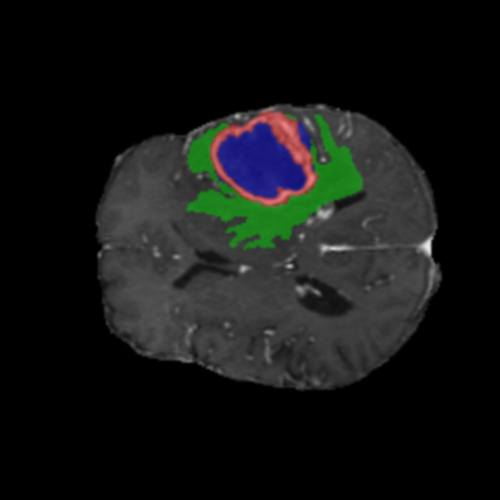

Mapas de Explicabilidad (Grad-CAM++)

Visualización de las regiones de atención del modelo que validan su razonamiento clínicamente relevante

Ejemplos HGG - Atención en Núcleo Necrótico y Tumor Realzado

HGG Grad-CAM++ 1 HGG Grad-CAM++ 2 HGG Grad-CAM++ 3 HGG Grad-CAM++ 4 HGG Grad-CAM++ 5 HGG Grad-CAM++ 6

Los heatmaps muestran que el modelo concentra su atención en las regiones de Tumor Realzado (rojo) y Núcleo Necrótico (azul), características patológicas clave de los gliomas de alto grado.

Validación con IA Explicable

El análisis Grad-CAM++ reveló que el modelo desarrolla automáticamente la capacidad de localizar las regiones tumorales. Para casos HGG, la atención se alinea fuertemente con las regiones de Tumor Realzado (ET) y Núcleo Necrótico (NCR). En contraste, los casos LGG muestran atención más difusa, principalmente concentrada en la región de Edema Peritumoral (ED), lo cual es consistente con la patofisiología conocida de los gliomas.

✅ Validación con IA Explicable